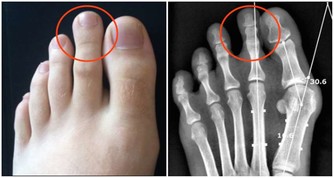

3、肺氣充足

通常說,底氣足的人聲音洪亮,底氣從何而來?從肺氣而來,如果一個人連說話都沒有力氣,就更別提身體健康了。